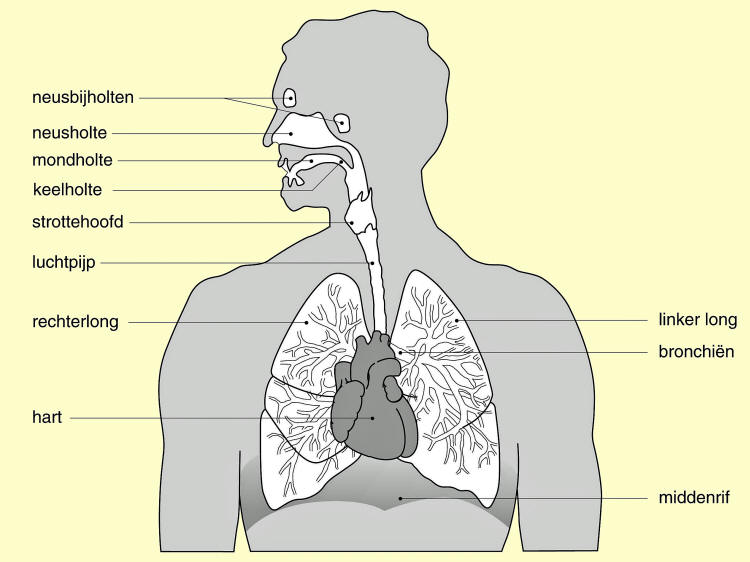

Longontsteking en bronchopneumonie. Infectie van het longweefsel vormt een longontsteking, maar als ook de kanalen (bronchi) die de lucht in de longen laten stromen aangetast zijn, spreekt men van bronchopneumonie. De oorzaken van deze infectie van de lagere luchtwegen zijn virussen, bacteriën en zelfs schimmels.

Longen En Luchtwegen

Longen